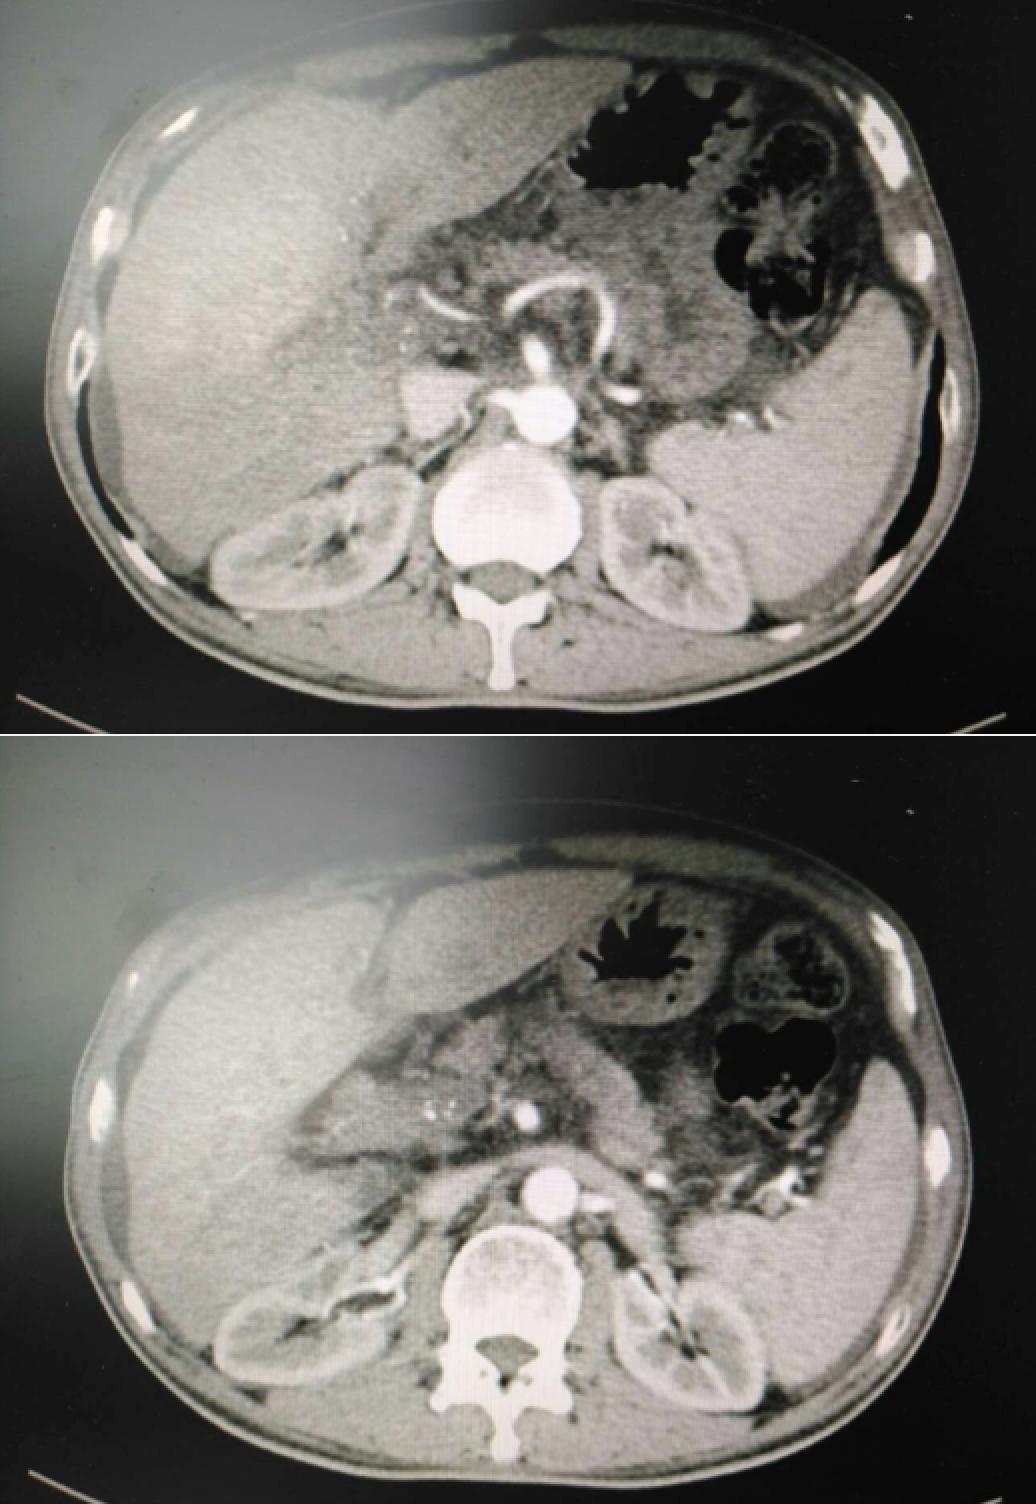

患者因纳差、烧心、腹痛、腹胀2月,于2016-01-17在某县人民医院行腹部CT示肝癌并门脉癌栓形成。分别于2016-01-22、2016-02-19于某市医院行两次TACE术(具体不详)。患者介入术后规律服用抗乙肝病毒、保肝、提高免疫力等药物治疗。2016-02-03至2016-04-30在某省立医院行5周期CIK免疫治疗。2016-05-18至2016-05-25于我院行射波刀治疗门静脉癌栓,具体放疗计划为:42Gy/7F。2016-06-24在我院行肝右动脉化疗栓塞术+肝右动脉灌注化疗术+间接门脉灌注化疗术,术中化疗总量,吡柔比星2mg、顺铂12mg、氟尿嘧啶250mg。分别于2016-05-10、2016-05-27、2016-06-13、2016-07-01、2016-07-27、2016-08-22、2016-09-19、2016-10-07、2016-10-19、2016-11-18、2016-12-18、2017-02-18行12周期免疫治疗。自2016-05-12起患者间断口服靶向药物阿帕替尼250-500mg/d,血压维持在220-130/95-70mmHg,血压升高期间伴上腹部不适,左侧为著,并向腰背部放射,偶尔反酸、烧心,剑突下疼痛,口服抑酸剂或进食后缓解,临床诊断为十二指肠溃疡,目前口服奥美拉唑、马来酸依那普利、氢氯噻嗪等药物对症降压。2017-03-02于我院行第二次肝右动脉化疗栓塞术+肝右动脉灌注化疗术+间接门脉造影术+肠系膜上动脉灌注化疗术。术中化疗总量,洛铂10mg、氟尿嘧啶500mg、吉西他滨400mg。目前间或皮下注射胸腺法新、重组人干扰素α-2b提高免疫力及慢性乙型病毒性肝炎治疗效果。

患者相关影像资料

4. 2017-3-15 DSA造影图中显示肿瘤组织血供一般,也未见癌栓显影,说明肿瘤组织或癌栓血供一般,也可能是靶向药物+栓塞化疗后,主要供血血管已闭塞,继续栓塞治疗效果有限。